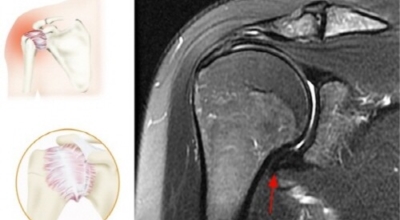

오십견이란 어깨의 통증과 어깨관절의 운동범위 제한을 특징으로 하는 질환으로 특히 50대 이후에 많이 발생함으로 오십견이라 이름이 지어졌으며 어깨관절이 얼어붙었다는 뜻으로 동결견(frozen shoulder)이라고도 합니다. 어깨관절의 운동성이 소실되기 때문에 옷 입기, 머리 감기, 물건 들기 등의 일상생활에 많은 어려움이 유발되며 통증으로 인해 잠을 못자는 경우도 대부분이 발생하게 되어요.

관절이 빳빳해진 느낌으로 오십견 증상을 방치했을 경우 관절이 빳빳해진 느낌이 들면서 어깨 움직임의 이동 범위에 점점 제한을 느끼게 된다고 합니다. 통증이 심한 경우에는 단순하게 옷을 갈아입거나 하는 행위를 할 때에도 통증 때문에 어깨를 움직이지 못하는 경우가 있겠습니다.